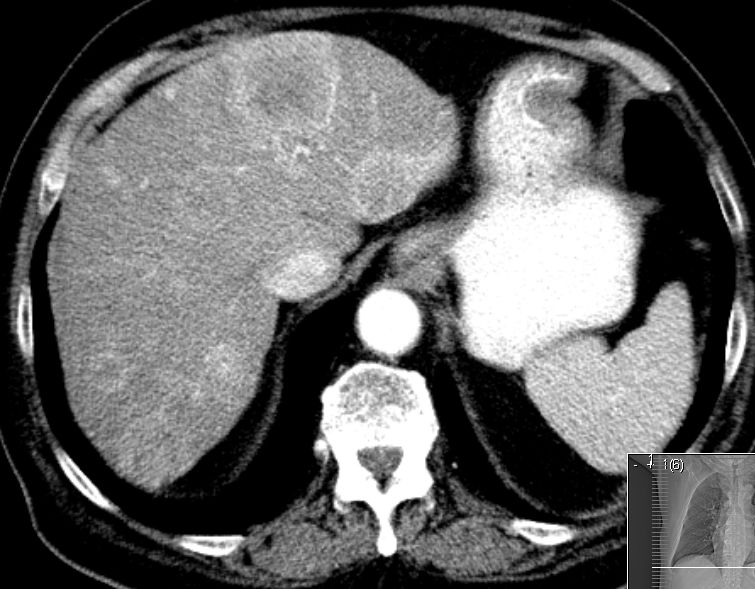

78-jähriger Mann, der 2 Jahre nach GIST des Dünndarms Lebermetastasen entwickelte.

Typisch ist die ausgeprägte hypervaskuläre Metastasenperipherie.![]() |